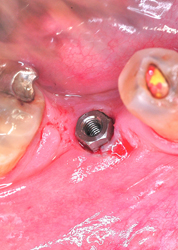

Es frecuente la remisión de pacientes a los que se les ha intervenido parcialmente, en base a sus requerimientos, olvidando los conceptos básicos de la fisiología normal del SEG(Sistema Estomatognático), y que terminan siendo motivo de una Rehabilitación Oral Integral , que debió ser concebida desde el principio de su tratamiento. Se presenta a la consulta un paciente derivado, portando dos puentes recientes de porcelana, con severas anomalías en su oclusión, aquejado de síntomas dolorosos en varias piezas dentarias, sobre todo a los cambios de temperatura y demás estímulos locales. Estudiado el enfermo radiográficamente, procedemos a desmontar los puentes encontrando debajo de uno de ellos un gran proceso carioso por filtración de la corona. Tallamos ambos maxilares y montamos un conjunto provisional a partir de un sencillo encerado realizado en clínica, el que usamos como férula radiográfica instalando en los sectores a implantar conos de gutapercha. Obtenemos imágenes de Dentascan Y procedemos a implantar mediante técnicas de Cirugía Minimamente Invasiva y Semi Sumergida y se toman impresiones mediante transfers intra operatoriamente. Realizamos un control mediante ortopantomografía. Mientras tanto se realiza en laboratorio un encerado para la confección de provisionales correctos. Dos meses después, se verifica la salud peri implantaria Y se instalan los nuevos provisionales sobre los abuttments ya construidos y los muñones tallados. Inmediatamente procedemos a tomar impresiones definitivas y contruir los núcleos de porcelana de alta densidad de la Guía Anterior (QUE ES LO PRIMERO QUE DEBEMOS RECONSTRUIR) y probarlos en boca para luego terminar la Guía Anterior y observar su adaptación y estética, para finalmente construir los cuadrantes posteriores y comprobar las disclusiones.